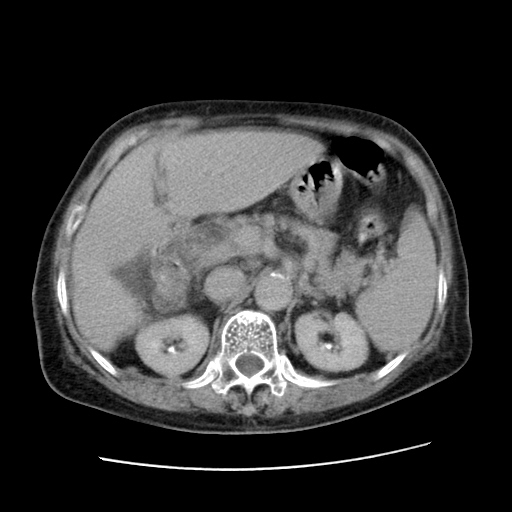

女,77.无不适

肝脏变异、异位胆囊,肝右叶肝内胆管结石并肝内胆管扩张。

肝右叶肝内胆管结石并肝内胆管扩张。

肝右叶肝内胆管结石并肝内胆管扩张

胆总管扩张

肝右叶肝内胆管结石并肝内胆管扩张。胆总管下段梗阻,考虑壶腹部占位。

右侧肝内胆管局限性扩张,其内密度不均匀,扩张的胆管壁增厚,考虑肝内胆管炎合并结石可能性大

肝右叶肝内胆管结石并肝内胆管扩张。胆总管下段梗阻,考虑壶腹部占位。支持